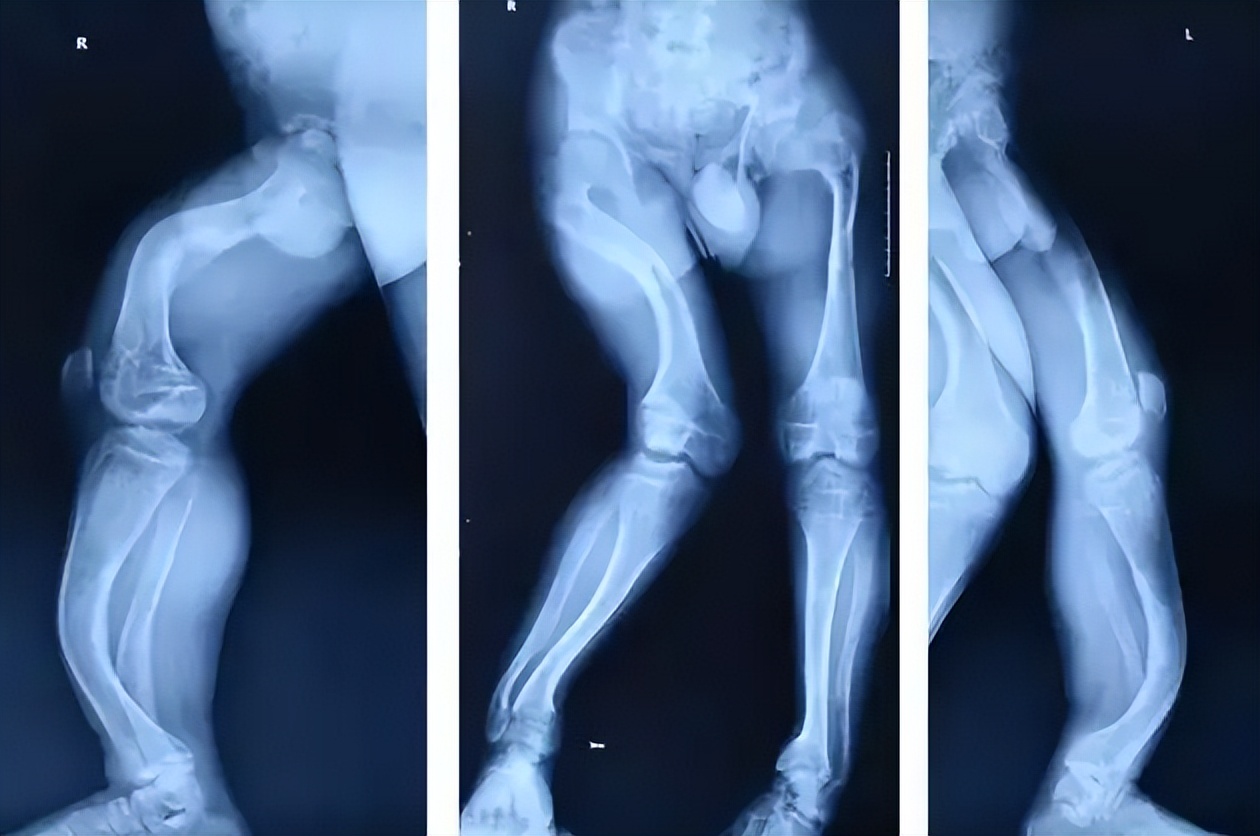

婴幼儿处于快速生长发育的重要时期,需要补充足够的钙质,婴幼儿缺钙会出现颅骨软化,方颅骨及鸡胸等骨骼畸形,缺钙严重者会发生下肢畸形,出现佝偻病(x型腿或O型腿)。

同时缺钙会影响婴幼儿身高及生长发育,而且会导致出牙迟、 厌食、多汗、烦躁、好哭、易醒、易惊吓、枕部脱发圈、佝偻病、骨骼畸形——如方颅、乒乓头、肋骨外翻、 O型腿或X型腿、肌张力低下、 运动机能发育落后、说话迟、免疫力低下等。